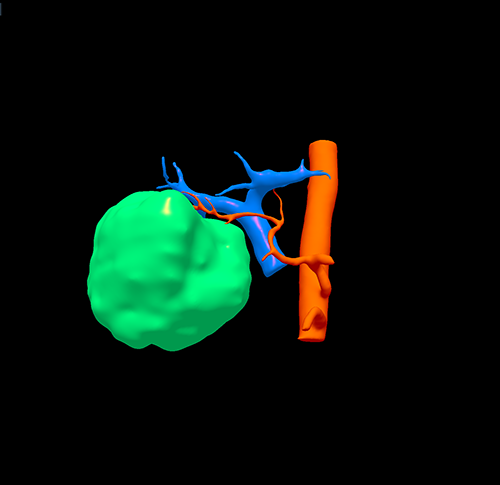

右肝癌----S567切除